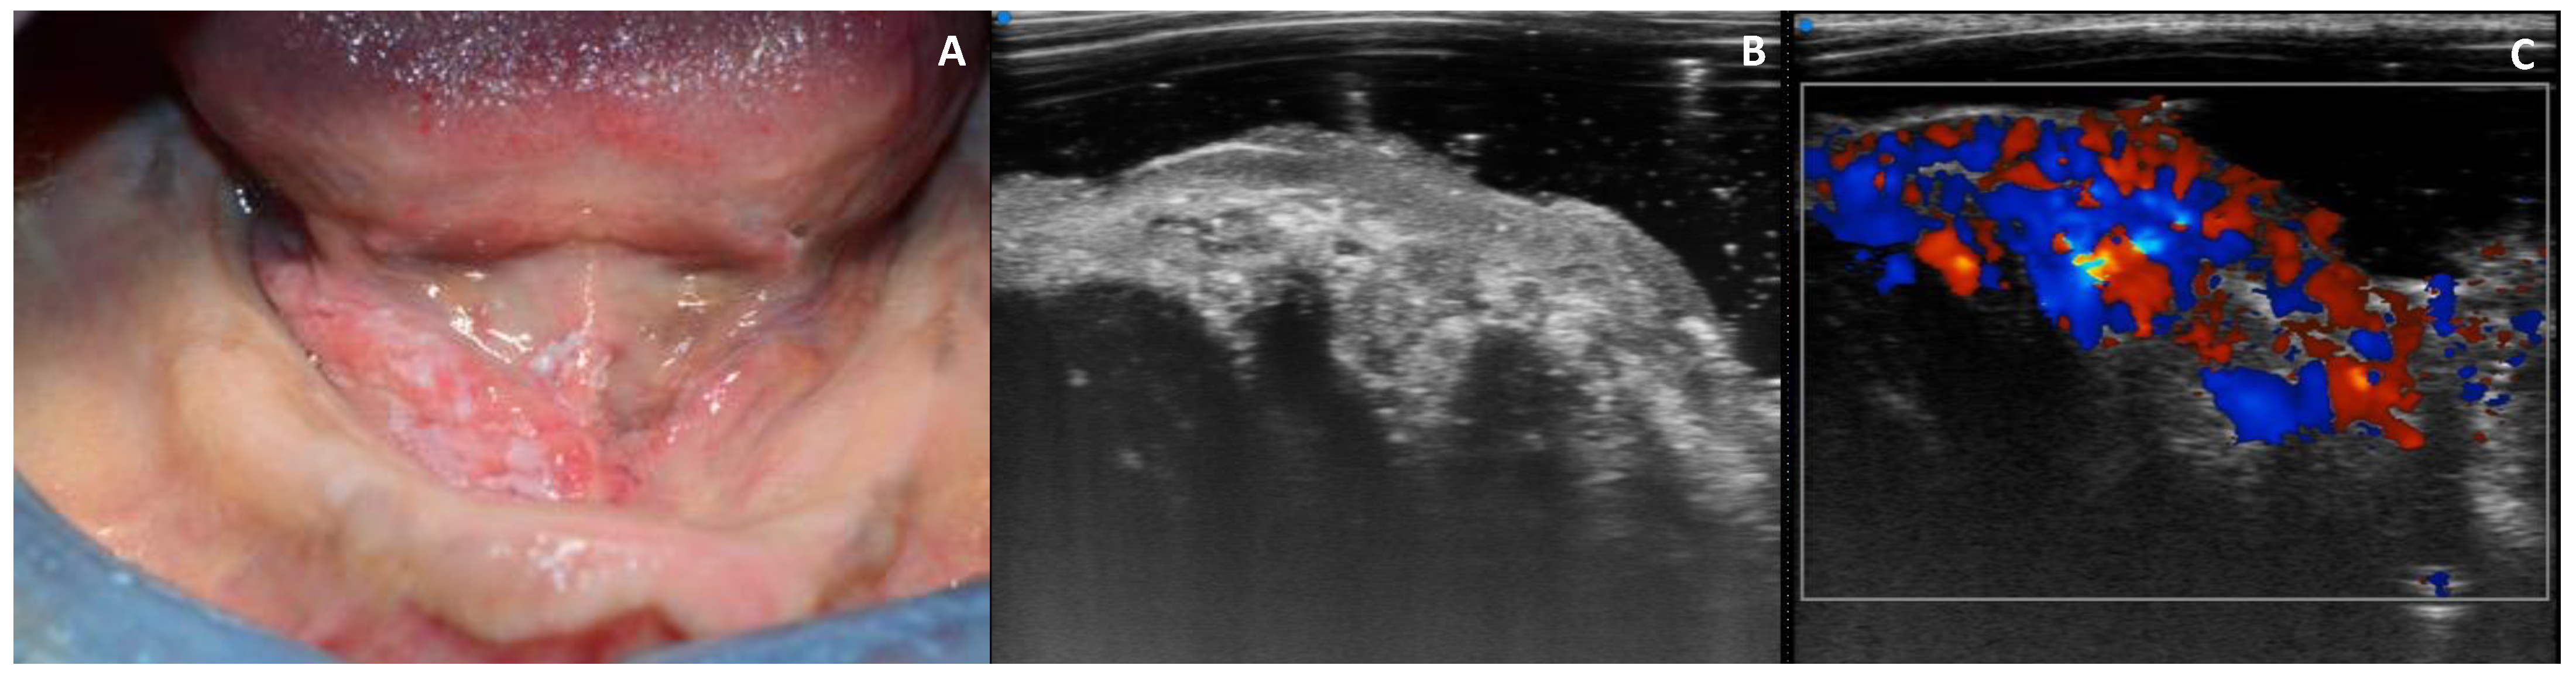

3.4. Echogenicity

3.5. Vascularization